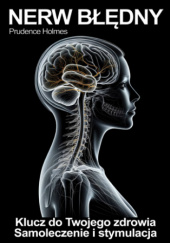

Nerw Błędny - klucz do zdrowia. Stymulacja, aktywacja i terapia nerwu błędnego

Prudence Holmes Wydawnictwo: Enbook zdrowie, medycyna 108 str. 1 godz. 48 min.

Odkryj sekrety jednego z najważniejszych nerwów w ludzkim ciele, który może być kluczem do poprawy Twojego zdrowia i samopoczucia. Ta przełomowa książka odkrywa, jak aktywacja i stymulacja nerwu błędnego może przynieść ulgę w stanach zapalnych, zmniejszyć stres, poprawić trawienie i nawet przyczynić się do lepszego snu. Autorzy, eksperci w dziedzinie medycyny integracyjnej, dzielą się praktycznymi technikami i terapiami, które pomogą Ci odblokować potencjał ukryty w Twoim ciele, otwierając drzwi do lepszego zdrowia psychicznego i fizycznego.

"Ta książka to prawdziwy przełom w naturalnym podejściu do zdrowia. Praktyki i terapie opisane przez autorów zmieniły moje życie!" - Dr Ava Green, ekspertka wellness i autorka bestsellerów.

"Wspaniale jest zobaczyć, jak dawne mądrości łączą się z nowoczesną nauką, by pomóc nam żyć pełnią życia. Ta książka to must-have dla każdego, kto szuka naturalnych sposobów na poprawę swojego zdrowia." - Leo Sunstone, znany guru zdrowego stylu życia.

"Nigdy nie przypuszczałam, że odpowiedź na tak wiele moich problemów zdrowotnych znajduje się wewnątrz mojego własnego ciała. Dzięki tej książce nauczyłam się, jak wykorzystać potęgę nerwu błędnego do poprawy mojego samopoczucia." - Maya Clearwater, znana joginka i nauczycielka medytacji.Średnia ocenTa książka nie została jeszcze oceniona NIE MA JESZCZE DYSKUSJI0,0 / 10